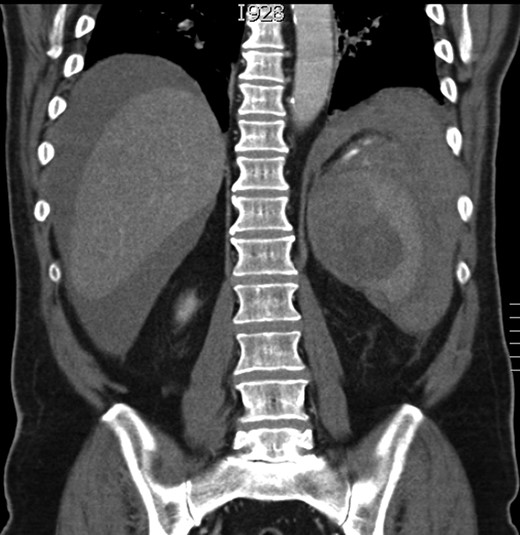

After initial resuscitation with intravenous fluids and starting of empirical antibiotics, an urgent CT scan of his abdomen and pelvis was obtained, which showed an abnormal spleen with signs of rupture and free intraperitoneal blood (Figs 1 and 2). On the basis of these findings, he was taken immediately to theatre after correction of his coagulation with 5 mg of vitamin K and 2000 units of Human Prothrombin Complex (Octaplex).

Coronal section of the CT scan showing the abnormal spleen and the haemoperitoneum.